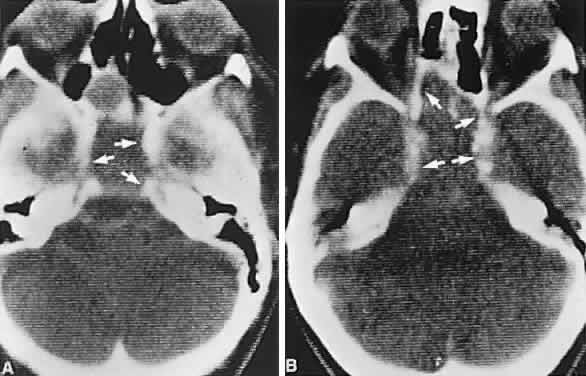

CT scanning retains special relevance to craniopharyngioma diagnosis, currently superior to MRI in detection of calcification and cyst formation (Fig. 7A to C); however, the extent of involvement of adjacent structures, that is, the optic chiasm, third ventricle, and intracavernous carotid artery, is more clearly delineated by MRI (Fig. 7D and E).93 Craniopharyngioma fluid collections are found to be uniformly bright on T2-weighted sequences, but on T1-weighted images, the signal intensity may range from hypointense to hyperintense, reflecting the heterogeneous contents of cysts. Because calcification and cyst formation are hallmarks of craniopharyngiomas, CT is more specific than MRI. At times, intrinsic infiltration of tumor may thicken the chiasm and contiguous optic nerve, a radiologic configuration that mimics glioma.94 Likewise, glioma may be simulated when the optic canal is invaded and enlarged, but accompanying bony erosion of the sella weighs heavily toward craniopharyngioma.

Fig. 7. Computed tomography scan of a large, multicystic craniopharyngioma. A. Axial section through the sella shows destruction of the bony skull base. Axial (B) and coronal (C) sections show cysts (white arrows) and calcification (arrowheads). Contrast-enhanced magnetic resonance imaging of the craniopharyngioma. Sagittal (D) and coronal (E) sections with gadolinium show solid and cystic (arrows) portions.